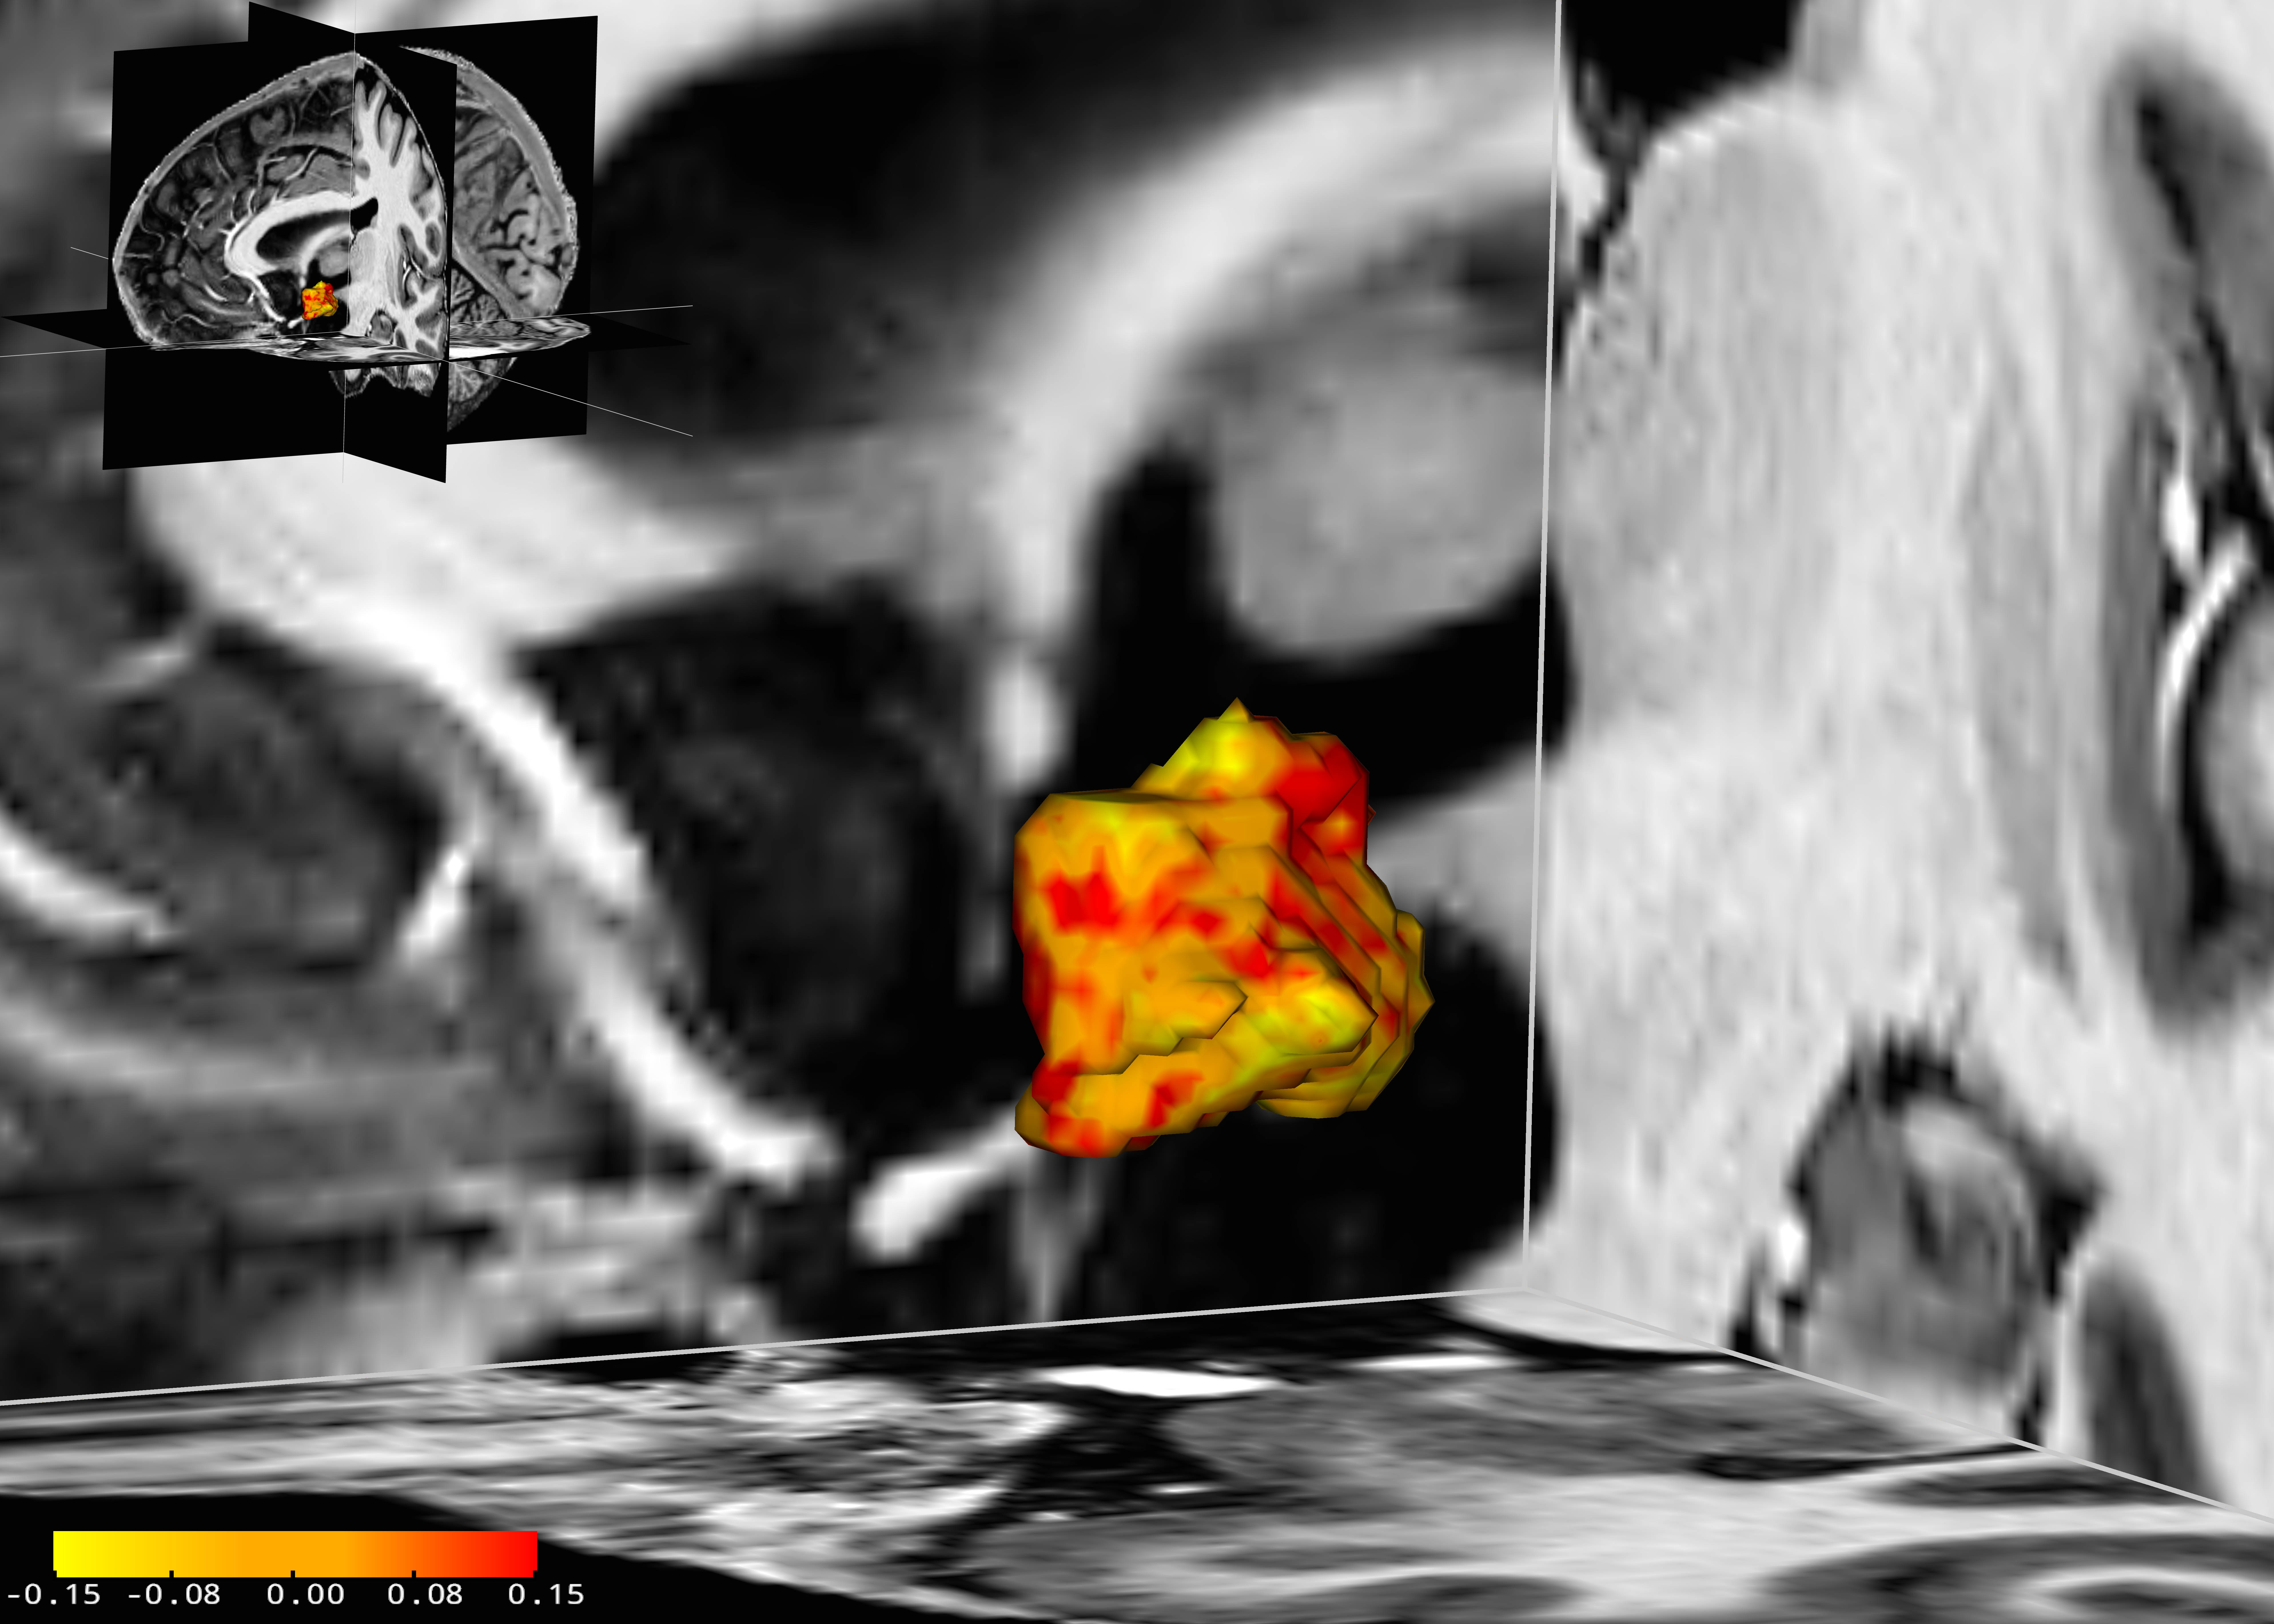

Wissenschaftler des Max-Planck-Instituts für Kognitions- und Neurowissenschaften (MPI CBS) in Leipzig und des Universitätsklinikums Leipzig haben nun in einer Studie mit insgesamt 84 Probanden herausgefunden, dass bei Personen mit einer sogenannten affektiven Störung der linke Hypothalamus um durchschnittlich fünf Prozent größer ist als bei Gesunden. „Wir haben beobachtet, dass diese Hirnregion sowohl bei Menschen mit einer Depression als auch mit einer bipolaren Störung, als zwei Formen der affektiven Störung vergrößert ist“, erklärt Stephanie Schindler, Doktorandin an beiden beteiligten Forschungseinrichtungen und Erstautorin der zugrundeliegenden Studie, die gerade im Fachmagazin Acta Psychiatrica Scandinavica erschienen ist. Dabei habe sich in einer der depressiven Patientengruppen auch gezeigt, dass diese etwa Ein-Cent-große Hirnregion umso größer war, je schwerer die Krankheit war. Medikamente wie Antidepressiva hätten wiederum keinen Einfluss auf die Größe des Hypothalamus gehabt.

Untersucht haben die Leipziger Wissenschaftler diese Zusammenhänge mithilfe der hochaufgelösten 7-Tesla-Magnetresonanztomographie. Die Schwere des psychischen Leidens ermittelten sie mithilfe von standardisierten Fragebögen und Interviews.

„Wir wissen bisher zwar noch nicht, welche Rolle der größere Hypothalamus innerhalb der Depression oder bipolaren Störung spielt. Frühere Studien haben jedoch gezeigt, dass er bei Betroffenen aktiver ist. Eine höhere Aktivität könnte möglicherweise zu plastischen Veränderungen und damit zu einem größeren Volumen dieser kleinen Hirnstruktur führen“, erklärt Stefan Geyer, einer der Studienleiter und Leiter der Forschungsgruppe Anatomische Analyse der Organisation des Gehirns des Menschen und nicht-humaner Primaten am MPI CBS.